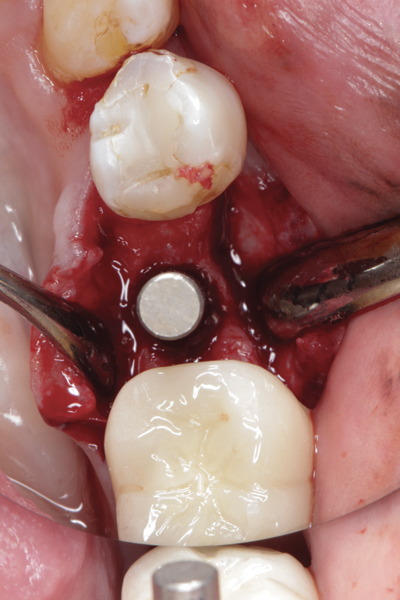

Fig 10. At 3 months postoperative, the flap was elevated, demonstrating a restored buccal plate of bone.

Figure 10

Fig 11. An implant was placed in regenerated bone.

Figure 11